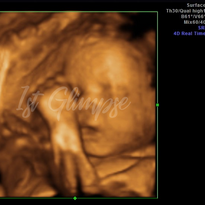

We offer the latest technology to provide you with quality imaging of your baby in 2D/3D/4D and HD ultrasounds. Enjoy viewing these beautiful babies all seen at our studio! Hydration is key for the clearest imaging of your baby in 3D and HD.

29-38 Weeks | HD